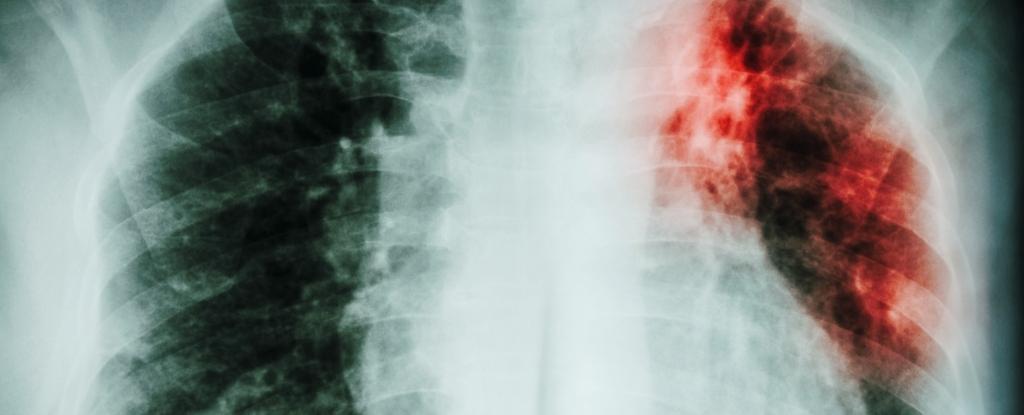

Туберкульоз (ТБ) вже багато років є основною проблемою охорони здоров’я, оскільки мільйони людей у всьому світі страждають від цієї смертельної хвороби. Хоча за останні кілька десятиліть було досягнуто значного прогресу у зниженні смертності від туберкульозу, нещодавній звіт свідчить про те, що ця тенденція, можливо, починає змінюватися на протилежну.

Звіт показує, що смертність від туберкульозу в Європі зросла на 4% у період з 2015 по 2019 рік, причому лише у 2019 році було зареєстровано 27 000 смертей. Це викликає занепокоєння, особливо з огляду на той факт, що туберкульоз є хворобою, якій можна запобігти і яку можна вилікувати. Зростання смертності значною мірою пов’язане із затримками в діагностиці та лікуванні, а також з появою резистентних до ліків штамів хвороби.